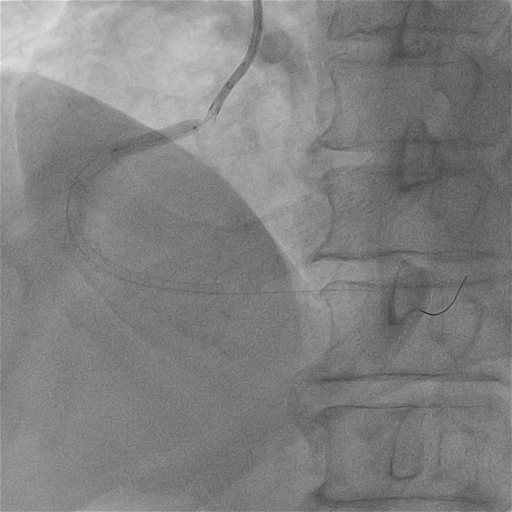

我院右冠基础造影

RCA:全程弥漫多处95%以上狭窄伴重度钙化,最重处次全闭塞,血流TIMI2级。

外院导丝可以到达远端,但是ELCA无法通过

我院尝试SION blue工作导丝通过病变,阻力明显,Fielder XT-R导丝可到达远端

尝试2.0mm球囊近段病变无法通过